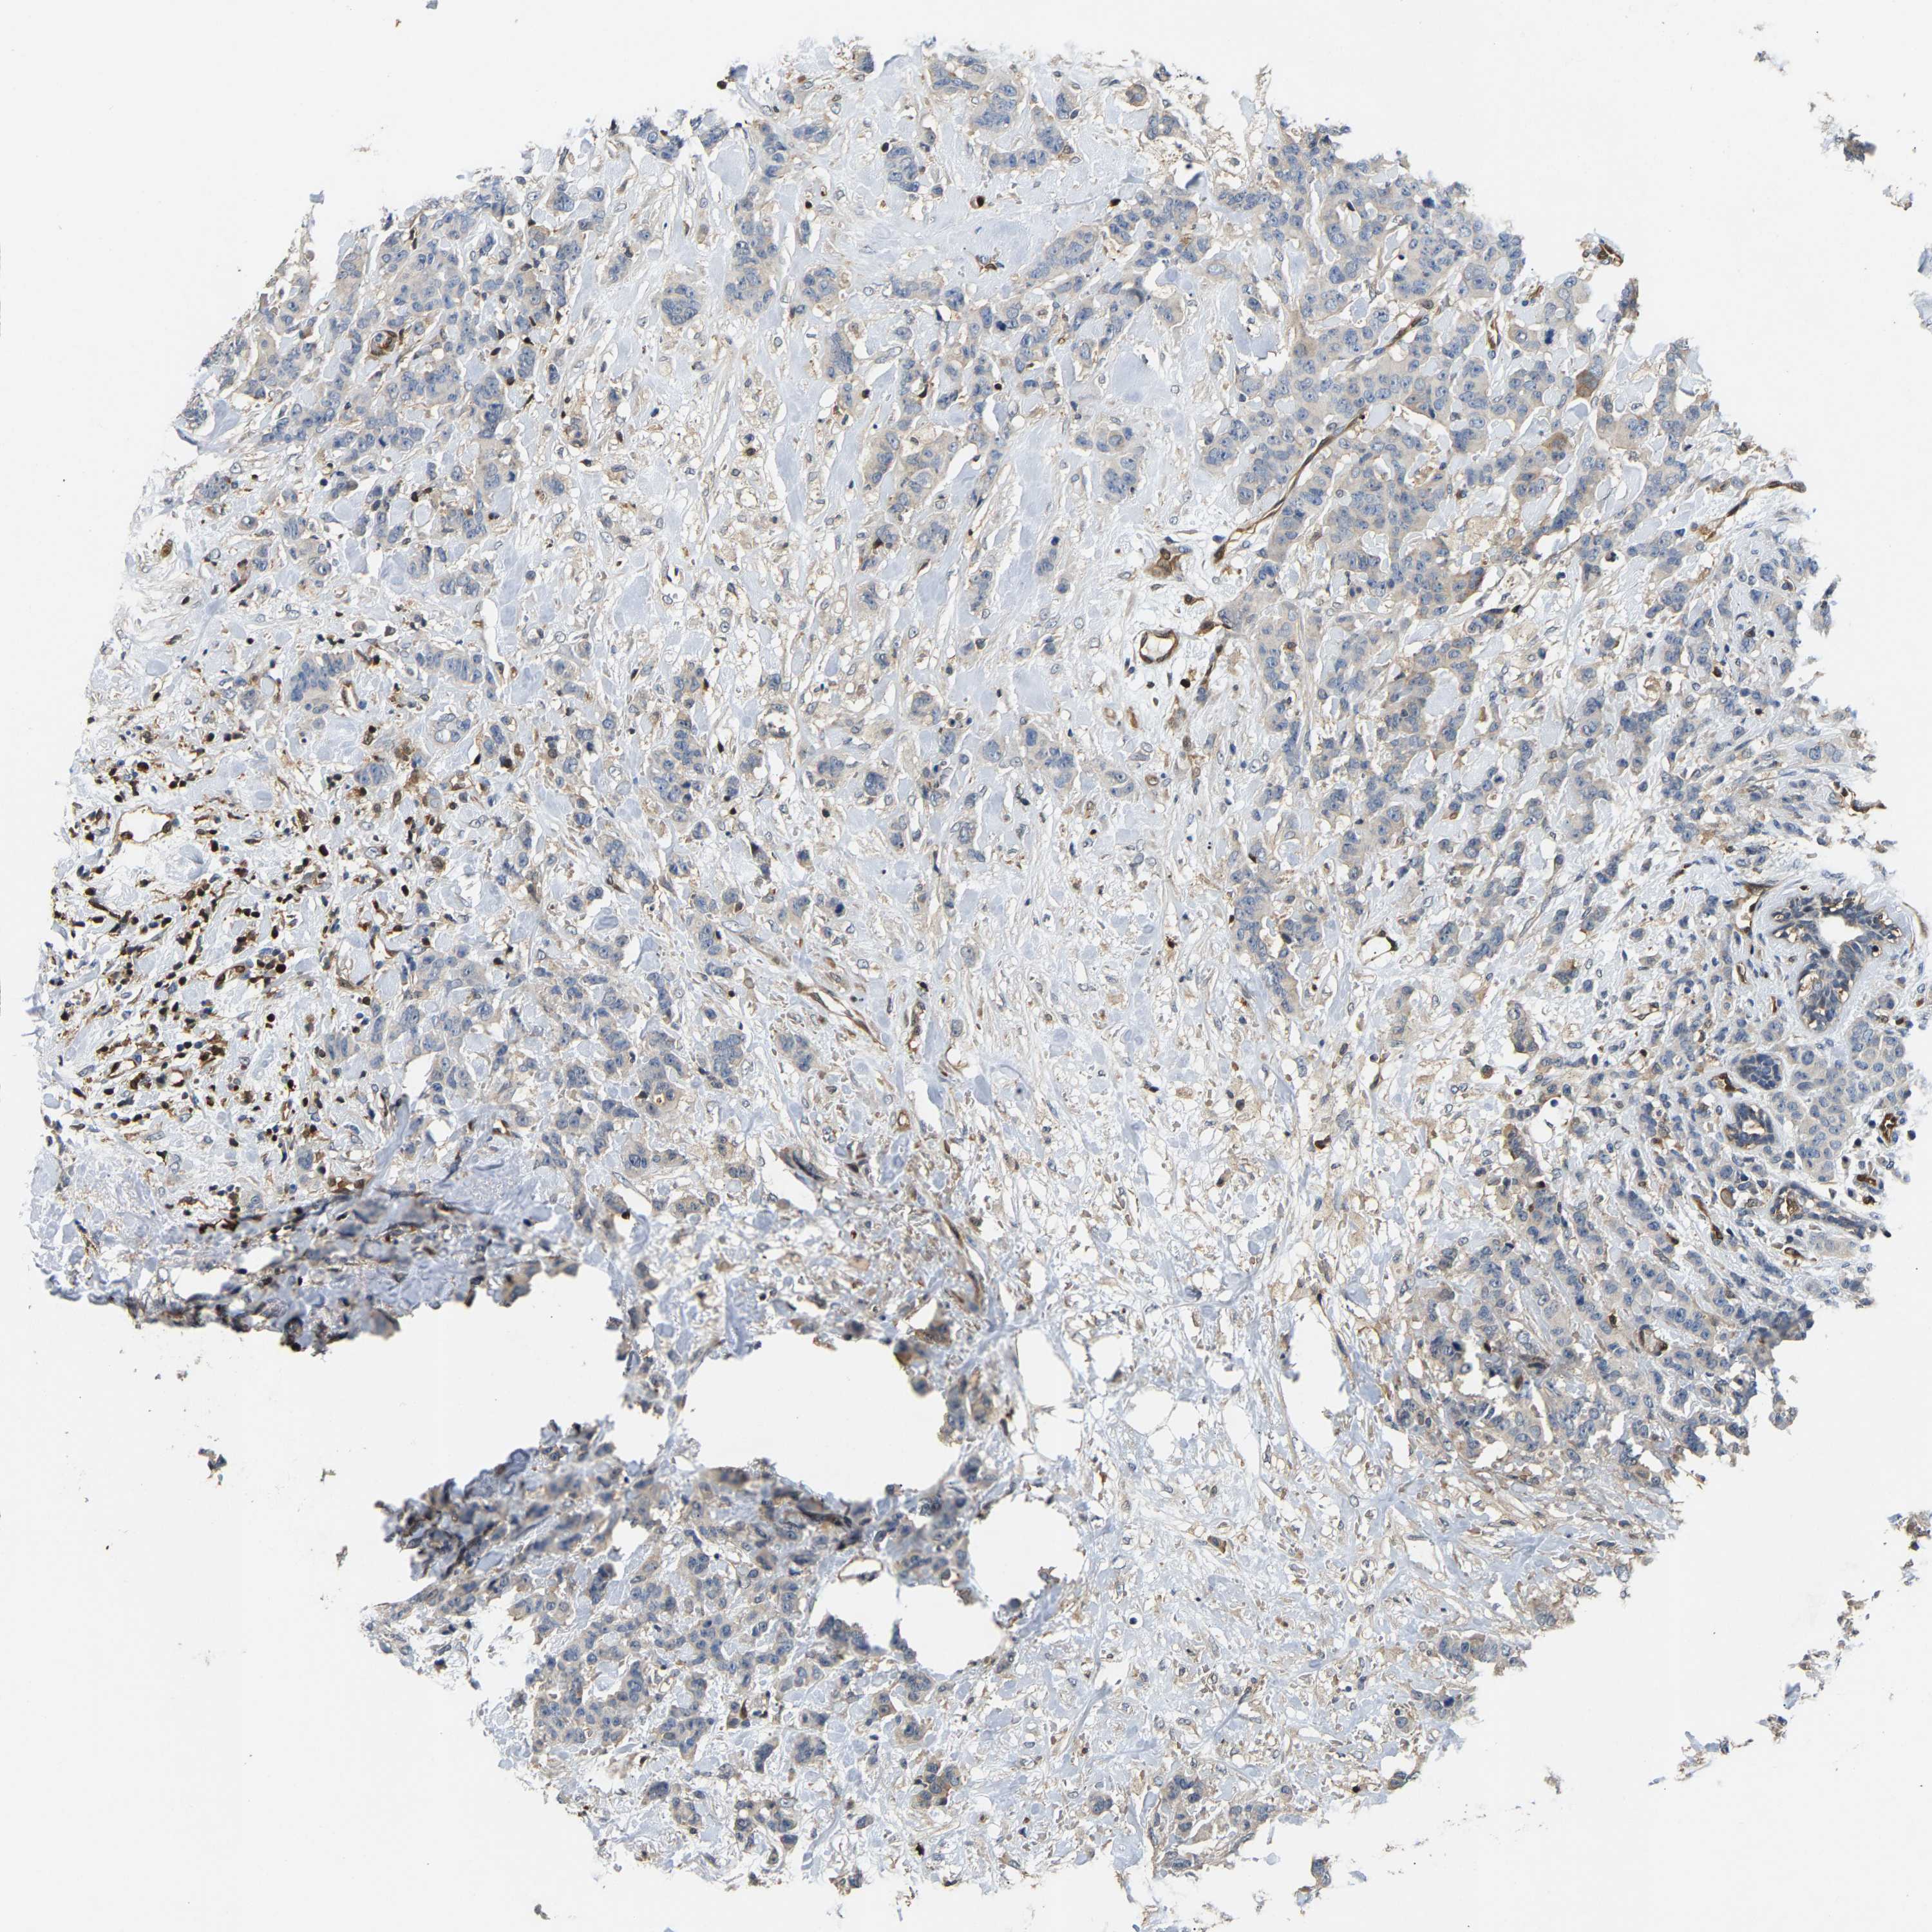

CANCER BREAST CANCER Show tissue menu

BRCA TCGA BRCA VALIDATION PROTEIN EXPRESSION